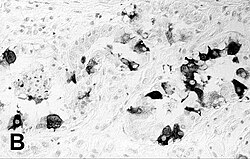

imunohistokemijsko bojenje pluća tuljana s PDV‑om | |